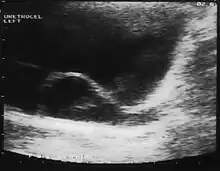

Since the advent of the ultrasound, most ureteroceles are diagnosed prenatally. The pediatric and adult conditions are often found incidentally, i.e., through diagnostic imaging performed for unrelated reasons.

A ureterocele is a congenital abnormality found in the ureter. In this condition the distal ureter balloons at its opening into the bladder, forming a sac-like pouch. It is most often associated with a duplicated collection system, where two ureters drain their respective kidney instead of one. Simple ureterocele, where the condition involves only a single ureter, represents only twenty percent of cases.